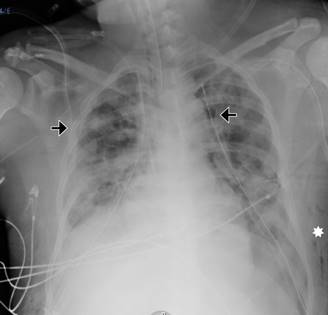

El caso que se presenta es el de un hombre de 42 años de edad, hospitalizado en la Unidad de Terapia Intensiva de Adultos (UTIA) por choque séptico y disfunción orgánica múltiple secundario a un absceso profundo de cuello ya drenado quirúrgicamente y con desarrollo de Klebsiella pneumoniae en cultivos del material purulento obtenido del absceso, hemocultivo, urocultivo y cultivo de secreción bronquial. El manejo brindado en la UTIA fue con base en paquetes, recomendaciones y metas de la campaña para incrementar la supervivencia en sepsis, con soporte multiorgánico, hemodiálisis intermitente por lesión renal aguda y ventilación mecánica invasiva por síndrome de insuficiencia respiratoria aguda grave (Figura 1). En su día siete de estancia en la UTIA con soporte mecánico ventilatorio invasivo en modo controlado con fracción inspirada de oxígeno (FiO2) al 60%, presión positiva al final de la espiración (PEEP) 10 cmH2O, frecuencia respiratoria de 18/minuto, presión control (PC) de 20 cmH2O, presentaba con estos parámetros una saturación por oximetría de pulso de 91% y relación PaO2/FiO2 160 mmHg. Desarrolló súbitamente incremento en las presiones de la vía aérea con desaturación progresiva, inestabilidad hemodinámica y aumento de volumen en el tórax anterior bilateral, presencia de crepitación a la palpación del tórax y abdomen, y disminución de ruidos respiratorios en ambos campos pulmonares a la auscultación. En rastreo ultrasonográfico del tórax con signo de «código de barras» en ambos hemitórax, por lo que se colocó de manera inmediata sonda endopleural en el hemitórax derecho percibiendo fuga aérea inmediata con mejoría parcial de la oxigenación por oximetría de pulso (SpO2 75%) e incremento en los parámetros de presión arterial media (PAM 50 mmHg). En la radiografía simple portátil del tórax con imagen de pneumotórax bilateral con reexpansión parcial del parénquima pulmonar derecho y pnemotórax izquierdo, por lo que se colocó otra sonda endopleural en el hemitórax izquierdo mejorando tras dicha intervención la SpO2 al 96% y la TAM a 70 mmHg. En control radiográfico simple, con reexpansión del parénquima pulmonar bilateral e imagen en relación enfisema subcutáneo extenso (grado V) (Figura 2A-C), por lo que se decidió realizar incisiones cutáneas infraclaviculares con disección roma subcutánea hasta la fascia pectoral mayor bilateral y colocación de drenajes de tipo BioVac, con lo cual se logró la resolución del enfisema subcutáneo en 24 horas (Figura 3). Se retiraron los drenajes BioVac 48 horas posteriores a su colocación sin recurrencia del enfisema subcutáneo.

Figura 1: Tomografía axial computarizada (ventana para pulmón) donde se observa imagen en vidrio esmerilado y múltiples áreas de consolidación pulmonar predominantemente en áreas declive bilateral.